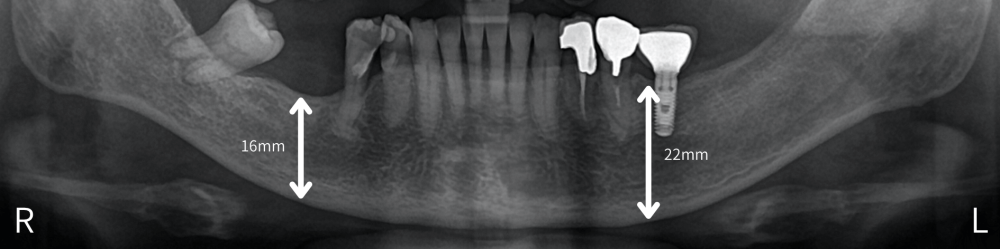

↑ 右側は骨がないのでインプラントはできないと言われご相談にいらした方のレントゲン画像。数年前に歯周病で歯を喪失したとのこと。

歯やインプラントがある左側は骨の厚みがあり、歯を失った右側は骨が痩せている。下顎の大きな神経管までの距離は約5mm。